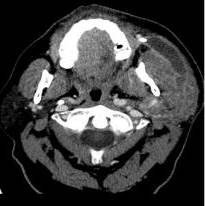

El caso que describimos a continuación, es el de un paciente masculino de 64 años de edad, que consultó por presentar aumento de volumen en región submaxilar izquierda de 8 años de evolución, con crecimiento progresivo en el último año, sin otra sintomatología asociada. Refiere antecedente de hipertensión arterial sistémica y diabetes mellitus, niega quirúrgicos, radioterapia. Hábito tabáquico durante 8 años, con índice paquete año (IPA) de 4. Antecedentes familiares de una hermana con cáncer gástrico y un hermano con cáncer de pulmón. Al examen físico de cabeza y cuello, se palpa tumor de 6 cm x 5 cm en región submaxilar izquierda poco móvil, dolorosa, sin adenomegalias cervicales, sin trismo, cavidad oral sin lesiones. Nasofibrofaringolaringoscopia sin alteraciones. Resto del examen físico sin alteraciones aparentes. Se le realizó ecosonograma de piel y partes blandas, donde se describe lesión ovalada heterogénea de predominio hipo-ecoico en región submaxilar izquierda, de márgenes parcialmente definidos, sin señal vascular al Doppler color, de 3 cm x 2,4 cm x 2,3 cm. Tomografía de cabeza y cuello se evidenció tumor en sólido con áreas quísticas de 5 cm x 4 cm en glándula submaxilar izquierda (Figura 1). Se realizó PAAF de lesión, la cual reporto Bethesda I.